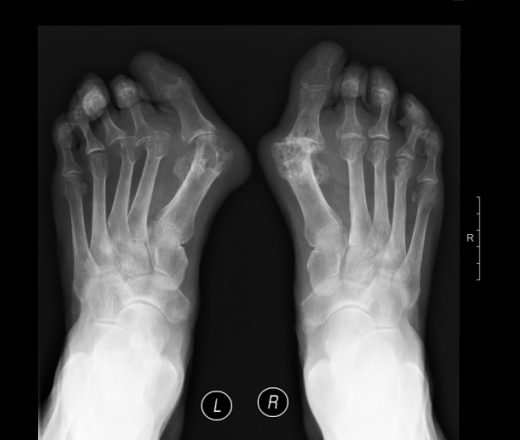

Пол пациента: Женский пол Тип патологии: Метаболическое заболевание Область исследования: Скелетно-мышечная система Методы исследования: Rg возраст 74 ,боли в суставах РА??? ID:63058 Цель публикации: Консультация Mon, 15/02/2016 - 16:14 #1 NIL Offline Last seen: 2 weeks 4 days ago Joined: 25.11.2013 - 20:50 Posts: 18208 В данном случае мне подагрический артирит милее "Слушай всех, прислушивайся к немногим, решай сам".© Mon, 15/02/2016 - 16:16 #2 Agr_Ai Offline Last seen: 3 months 2 weeks ago Joined: 02.09.2014 - 14:10 Posts: 1393 Я за ревматоидный. Кисти бы доснять. Mon, 15/02/2016 - 16:46 #3 Сергей Кузьминов Offline Last seen: 1 year 1 month ago Joined: 06.10.2012 - 15:51 Posts: 11813 Agr_Ai wrote: Я за ревматоидный. Кисти бы доснять. +1. Mon, 15/02/2016 - 17:15 #4 maker4ik Offline Last seen: 8 years 8 months ago Joined: 19.10.2011 - 17:49 Posts: 2682 Сергей Кузьминов wrote: Agr_Ai wrote: Я за ревматоидный. Кисти бы доснять. +1. +1 Mon, 15/02/2016 - 17:58 #5 Михаил66676 Offline Last seen: 6 years 3 months ago Joined: 28.11.2015 - 13:37 Posts: 16 Тофусы есть Tue, 16/02/2016 - 09:09 #6 urievich Offline Last seen: 2 months 4 weeks ago Joined: 28.07.2015 - 07:42 Posts: 435 За подагру. Что с анализам /мочевая кислота, СРБ?,/ Tue, 16/02/2016 - 09:11 #7 перчик Offline Last seen: 1 month 2 weeks ago Joined: 06.03.2014 - 12:16 Posts: 721 urievich wrote: За подагру. Что с анализам /мочевая кислота, СРБ?,/ Это первичная больная, анализов пока нет, но суставной синдром много лет)) Tue, 16/02/2016 - 09:12 #8 перчик Offline Last seen: 1 month 2 weeks ago Joined: 06.03.2014 - 12:16 Posts: 721 Михаил66676 wrote: Тофусы есть тофусы в головках плюсневых костей? я вижу вроде слева один Tue, 16/02/2016 - 16:43 #9 Елена Александрова Offline Last seen: 3 years 7 months ago Joined: 17.01.2016 - 10:13 Posts: 4 Мне кажется все же подагрический+ статическая деформация стоп Wed, 17/02/2016 - 07:52 #10 Sushkov IV Offline Last seen: 7 years 3 months ago Joined: 03.08.2015 - 22:23 Posts: 582 К сожалению без биохимии не доказать, но мне тож подагрический здесь милее по картинке, хоть и такая распространенная форма поражения для него менее характерна. Wed, 17/02/2016 - 08:00 #11 Лейман Иван Offline Last seen: 3 months 1 day ago Joined: 09.01.2014 - 07:54 Posts: 1190 А я за подагричесикй Thu, 18/02/2016 - 01:57 #12 Игрок Offline Last seen: 9 years 1 month ago Joined: 15.10.2015 - 17:29 Posts: 2321 Ставлю на двоих! Страсть - сила любви! Nobody

В данном случае мне подагрический артирит милее

Я за ревматоидный. Кисти бы доснять.

Тофусы есть

За подагру. Что с анализам /мочевая кислота, СРБ?,/

Это первичная больная, анализов пока нет, но суставной синдром много лет))

тофусы в головках плюсневых костей? я вижу вроде слева один

Мне кажется все же подагрический+ статическая деформация стоп

К сожалению без биохимии не доказать, но мне тож подагрический здесь милее по картинке, хоть и такая распространенная форма поражения для него менее характерна.

А я за подагричесикй